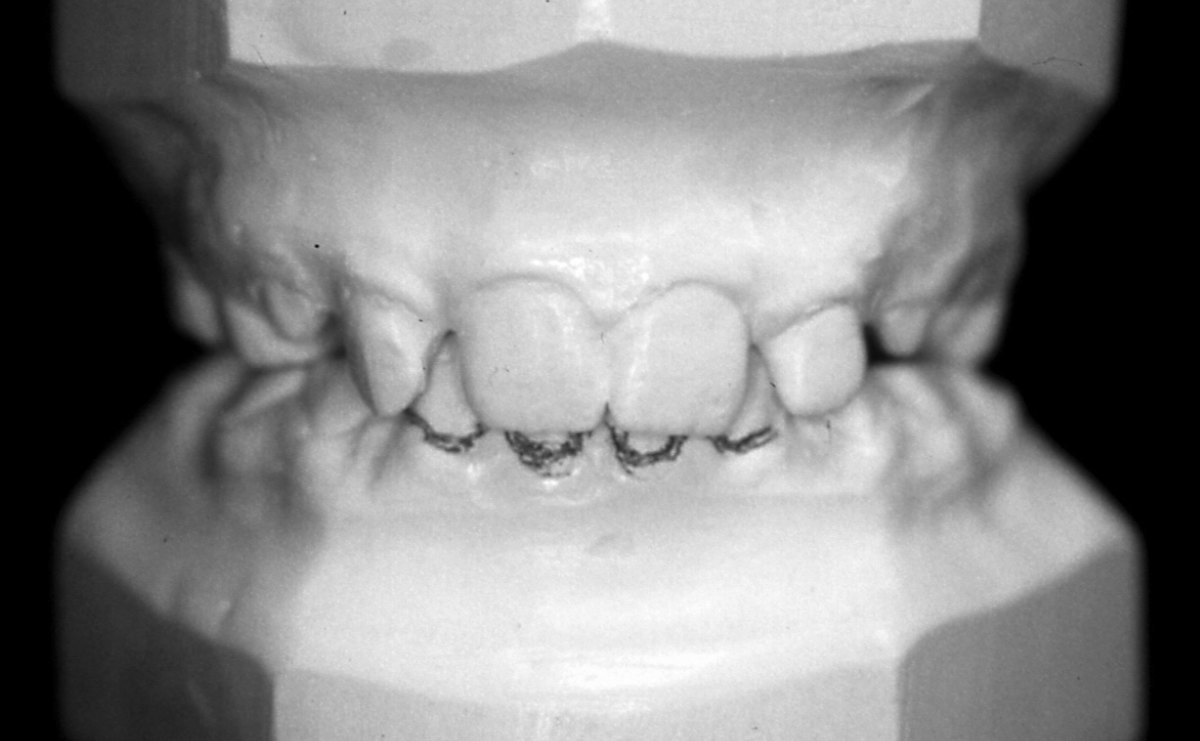

Наскоро излезе книгата на д-р Мишел Монто Нашите зъби - портал към здравето. Д-р Татяна Тасева, медицински консултант на книгата, любезно се съгласи да отговори на няколко въпроса. Защо книгата не е това, което изглежда; как мъдростта на зъбите (дентософията) може да промени целия живот на човека – вече и в България; как психоемоционалното състояние зависи от хармонията в устата и още можете да прочетете тук.

От баланса на нашите зъби зависят психичното здраве и емоционалният ни комфорт (интервю)